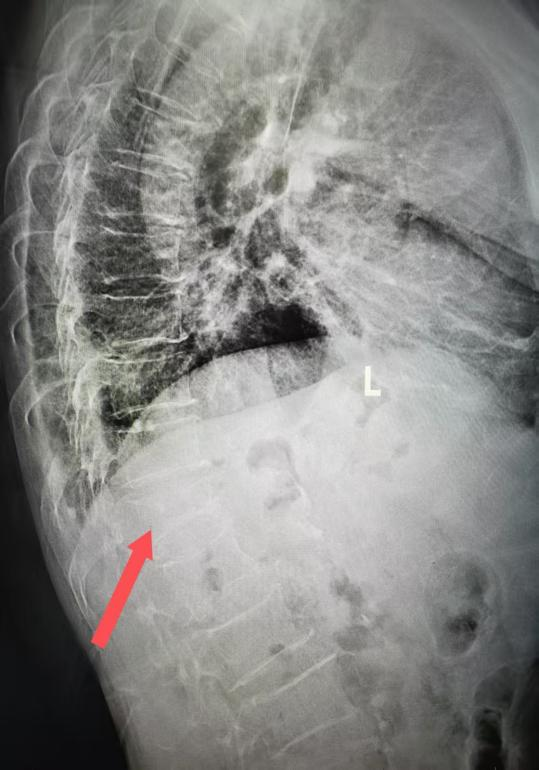

术前CT三维重建显示 第12胸椎压缩骨折(箭头所示)